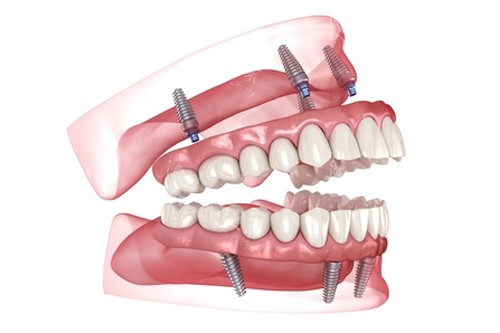

全口种植牙前后

全口种植

全口种植牙解析图